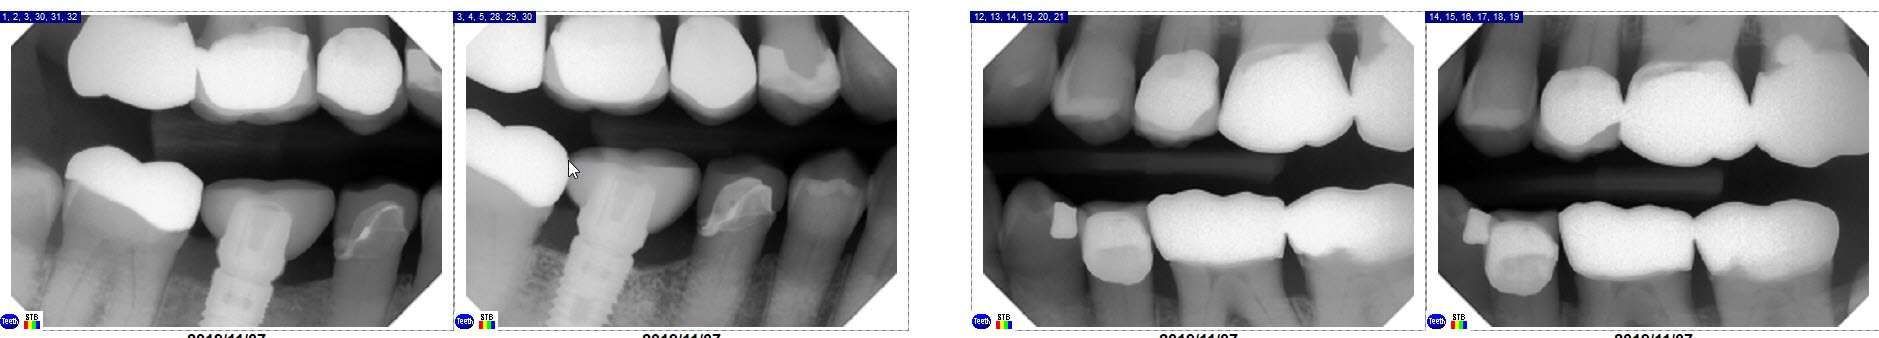

Periapical X-rays

Periapical x-rays capture the full length of 1 or more teeth, so that we can see the apex, or end, of the root. That’s where we look for signs of a tooth abscess, or infection. We also use them, as in this case, to make sure that dental implants are fully integrated in the bone.